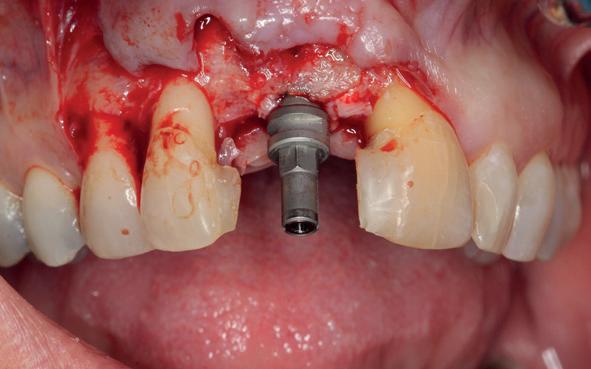

Er werd meer bekend over de gedragingen van het bot rond de “microgap” en daarmee kwam er meer begrip over hoe een implantaat goed te plaatsen in de esthetische zone. In het midden van de jaren negentig kwam daar de kennis bij hoe, op een verantwoorde manier en met behulp van guided-bone-regeneration, een implantaat in de esthetische zone te plaatsen (afbeelding 6-10).

Van vooral functionaliteit verschoof de indicatie naar esthetiek. De zachteweefselchirurgie en vaak voorbehandeling van zachte weefsels voor implantologie kreeg veel meer aandacht (afbeelding 11-14).